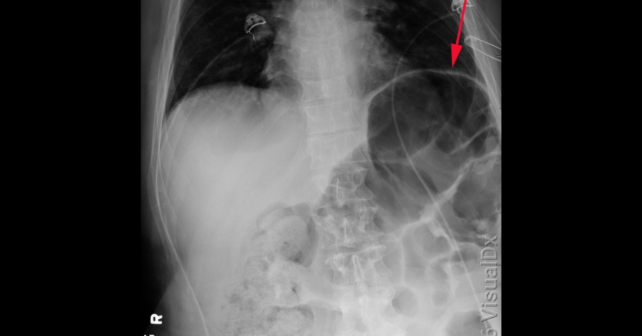

Question: A 76 year old man presents with abdominal pain, nausea, and vomiting. The abdominal radiograph is shown. What is the diagnosis?

ACEP Now: April Digital 02-Da. Cecal volvulus

b. Large bowel obstruction

c. Small bowel obstruction

d. Sigmoid volvulus